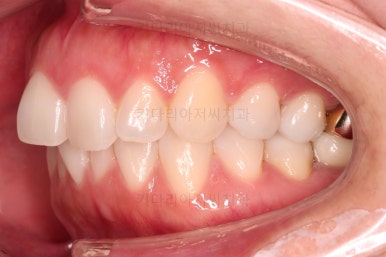

오늘 부산부분치아교정 키다리아저씨치과에서 소개해 드릴 환자분은 앞니가 삐뚤고, 토끼처럼 나와있다고 교정치료를 원하셨던 분입니다.

웃을 때 모습에서 앞니가 조금 삐뚤어 미적으로 좋지 못하고, 특히나 대문니가 더 튀어나와 강조되어 보이고 유달리 커보이는 효과까지 주네요.

어금니의 맞물린은 100점은 아니지만 생활하기에 크게 나빠보이지 않고요.

특히 임플란트도 있는 상황이었기 때문에 굳이 어금니까지 교정할 필요는 없어보였어요.

앞니 부분교정으로 치료계획을 세웠는데 다른 분들에 비해 난이도가 높은 치료가 예상되었던 이유는 우측 상단의 사진에 선 그어놓은 부분을 보시면 어금니에 비해 아래앞니가 약간 솟구쳐 높이가 맞지 않다는 점이었어요.